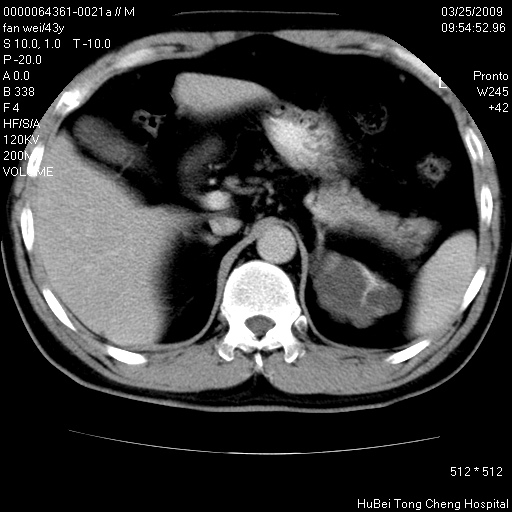

双肾ct轴位平扫+增强扫描(层厚10mm,螺距1.0,重建间隔10mm),图像如下:

多囊肾的影像诊断标准:有阳性家族史,年龄<30岁,单侧或双侧肾脏有两个肾囊肿;30~59岁,两侧肾脏各有两个肾囊肿;60岁以上,每侧肾脏有4个囊肿。敏感性和特异性达86%和80%。

此病例影像诊断符合,要结合家族史,腰痛、血尿、尿路感染史,有无高血压等综合判断,如无相应的临床症状,本身病变也无意义了(个人观点)

左肾体积变大,支持多囊肾。

双侧多囊肾!